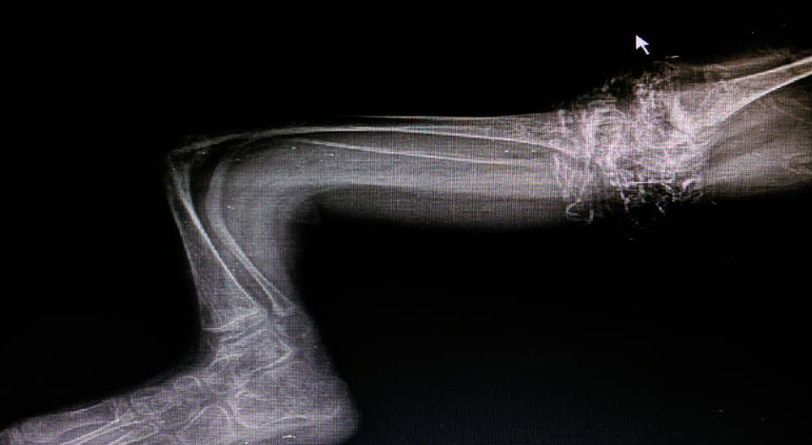

Osteogenesis imperfecta or Type l collagen,the most common inherited disease and cause by diffeciencies of synthesis of tupe l collagen

Xray

Dignosis